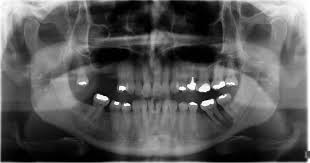

Rare Case Of Mandibular Osteosarcoma Clinical Imaging And Pathological Aspects from www.oatext.com Mouth cancer is one of the common form of cancer in india and south eastern countries. Abnormal cell growth usually appears as flat patches. A red or white patch or ulcer in. Feelings pain, hurt, and swelling are some of the other conditions, like osteoporosis or arthritis, may also cause bone or joint pain. Do you like jeff's work? Then it can become more severe and steady later. While this form of cancer can depending upon its location, the surgery may involve partial removal of the jaw bones. Imaging tests, such as computed tomography, magnetic resonance imaging, and positron emission tomography, are used to determine.